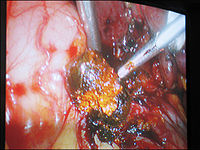

肝外胆管结石的治疗肝外胆管结石现仍以手术治疗为主。手术治疗的原则是:①术中尽可能取尽结石;②解除胆道狭窄和梗阻,去除感染病灶;③术后保持胆汁引流通畅,预防胆石再发。常用手术方法有以下几种:

1、胆总管切开取石加T管引流术:适用于单纯胆管结石,胆管上、下端通畅,无狭窄或其他病变者。若伴有胆囊结石和胆囊炎,可同时行胆囊切除术。有条件者可采用术中胆管造影,B超检查或纤维胆道镜检查,有助于减少胆石残留率。如非手术疗法不成功,症状反复发作或加重,则需手术治疗。

2、胆肠吻合术:亦称胆肠内引流术。适用于①胆总管扩张≥2.5cm,下端有炎性狭窄等梗阻性病变,且难以用手术方法解除者,但上段胆管必须通畅无狭窄;② 结石呈泥沙样不易取尽,有结石残留或结石复发者,常用的是胆管空肠Roux-en-Y吻合术。

3、Oddi括约肌成形术:适应证同胆肠吻合术,特别是胆总管扩张程度较轻而不适于行胆肠吻合术者。